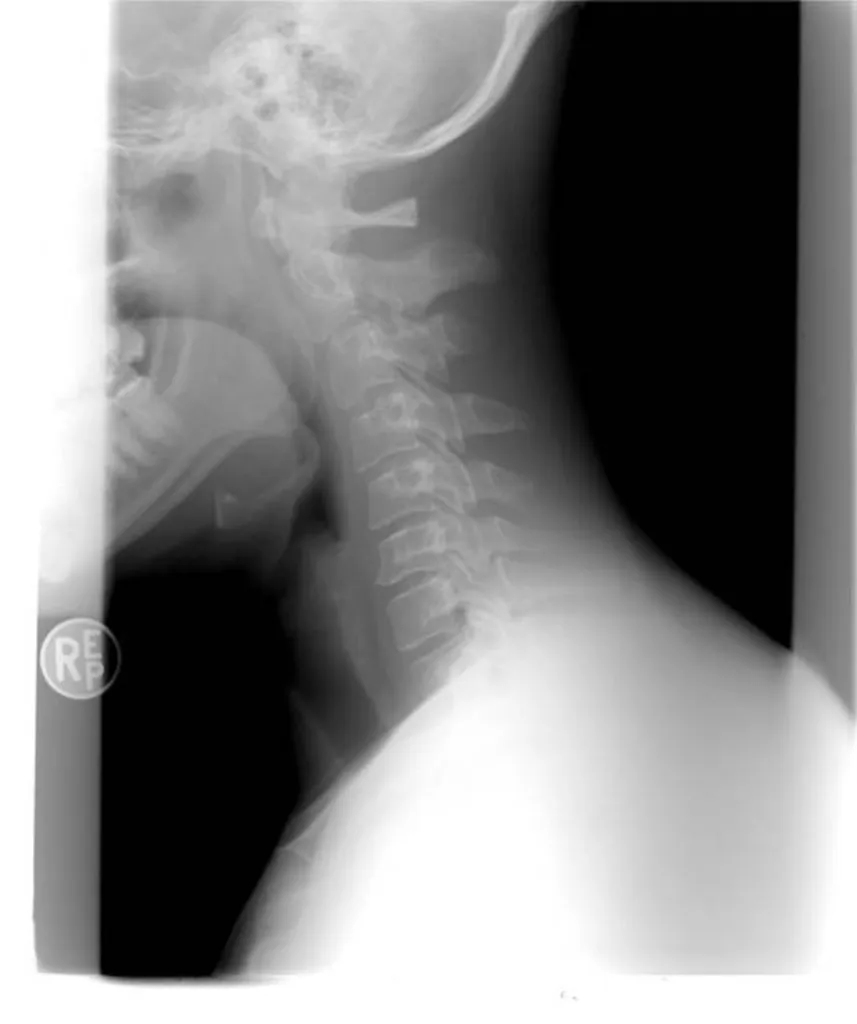

avocat de victime d’accident de la route en voiture, ayant subi un coup du lapin à Marseille

Montants d’indemnisation du dommage corporel de victimes d’accident de la route en voiture subissant un coup du lapin cervical lors d’un choc arrière selon notre cabinet d’avocat à Marseille

La victime d’accident de la route subissant un coup du lapin ou entorse cervicale lors d'un choc arrière en voiture sur l’autoroute à Marseille, a droit à l’indemnisation de son dommage corporel, sur le fondement de la loi du 5 juillet 1985, dite aussi loi Badinter. Ce type d’accident entraîne en...

Avocats de victimes d’accident de la route en voiture à Toulon ayant subi un coup du lapin.

11 628 euros alloués à une victime d’accident de la route en voiture à Toulon ayant subi un coup du lapin en réparation de son dommage corporel par l’intermédiaire de notre cabinet d’avocats

Par procès-verbal de transaction du 8 février dernier, notre cabinet d’avocats a obtenu la somme de 11.628 € à titre d’indemnisation du dommage corporel d’une victime d’accident de la route en voiture à Toulon, ayant subi un coup du lapin. La victime souffrait, depuis l’accident de la circulation ...

Avocat pour l'indemnisation d'une entorse cervicale en cas d'accident de la route à Marseille

16 918 € d’indemnisation versées à un chauffeur VTC victime d’accident de la route, ayant subi une entorse cervicale à Marseille

Notre Cabinet a obtenu le versement de la somme de 16 918 € à titre de dommages intérêts en indemnisation du préjudice corporel d’un chauffeur VTC ayant subi un accident de la route à Marseille, précisément un choc arrière, entrainant une entorse cervicale.L’indemnisation du dommage corporelle de ...

15 037 € de dommages intérêts alloués à une victime d’accident de la route conducteur, ayant subi une entorse cervicale à Marseille.

15 037 € de dommages intérêts alloués à une victime d’accident de la route conducteur de voiture, ayant subi une entorse cervicale à Marseille.

Le conducteur de voiture victime d'accident d'accident de la route à Marseille ayant subi une entorse cervicale a droit à l'indemnisation de son dommage corporel, sur le fondement de la loi du 5 juillet 1985, dès lors qu'il n'a pas commis de faute de conduite.Notre cabinet d’avocat a obtenu réce...